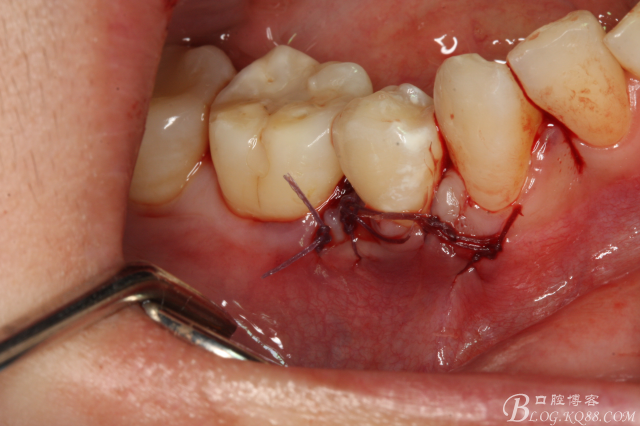

圖16.取出45牙根,牙槽窩完整、不變形。

圖19.縫合

圖20.拔除的45牙根。

微創(chuàng)拔牙不僅在種植外科需要最大限度的保留骨組織。同樣,在正畸領(lǐng)域,微創(chuàng)拔牙對骨組織的后期改建和正畸效果的好壞也至關(guān)重要。